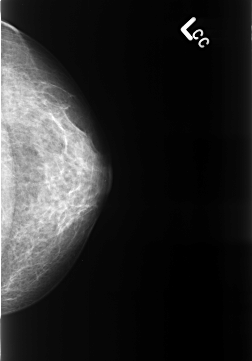

Volume: benign_without_callback_01 Case: B-3237-1

B_3237_1.LEFT_CC

PATIENT_AGE 46

DENSITY 3

LEFT_CC LINES 4328 PIXELS_PER_LINE 3024 BITS_PER_PIXEL 12 RESOLUTION 50 NON_OVERLAY

LESION_TYPE MASS SHAPE FOCAL_ASYMMETRIC_DENSITY MARGINS N/A

ASSESSMENT 2

SUBTLETY 4

PATHOLOGY BENIGN_WITHOUT_CALLBACK